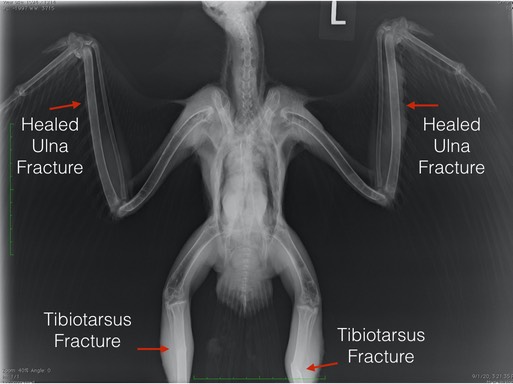

There are numerous abnormalities visible in the radiograph below (poorly formed and/or damaged joints) in addition to the four fractures noted by the arrows. The hawk was found as a downy chick, having been blown from its nest in a storm. Sadly, the finders were told by two wildlife agencies that the nestling was too young to rehabilitate and they should let nature take its course. Instead, they fed it chicken, pinkie mice and steak for three months, not realizing that was a death sentence as well. There is essentially no calcium in a diet of meat. Red-tailed Hawks are able to eat all parts of small rodents, including the bones, within days of hatching. When admitted, 20-504 could not stand normally and could fly only a few feet. The damage caused by MBD is not reversible.